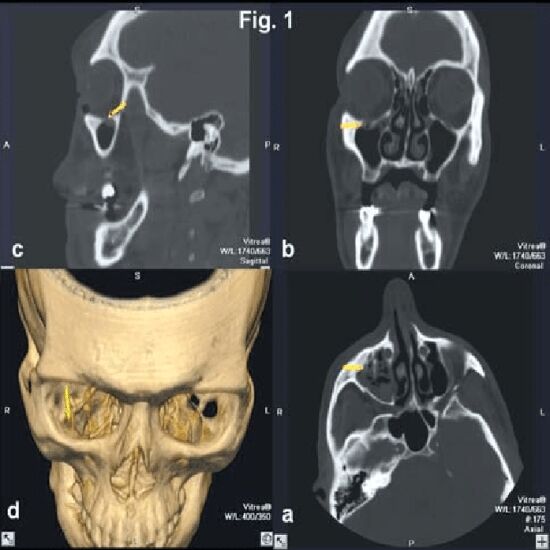

3D CT Orbit is an imaging scan to visualize the bony structure of orbit and pathology conditions in 3D reconstruction.

3D CT Orbit is a diagnostic modality. This imaging technique helps your doctor visualize the internal structures including the bony structure of the orbit. It helps determine any pathological conditions in the form of 3D reconstruction.

The scan can be used to-

• Determine fracture of the orbit

• Identify the effects of trauma

• Diagnose any congenital defect